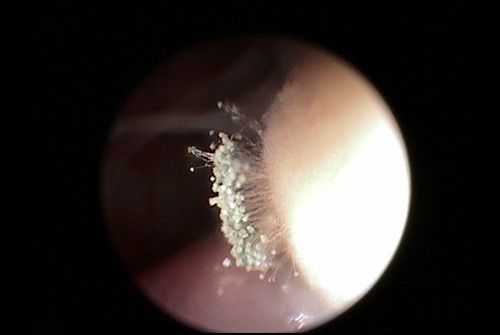

• Aspergillose

Die Endoskopie hilft auch bei inneren Erkrankungen wie der Aspergillose. Man erhält Einblicke über z.B. das Ausmaß und kann weitere Maßnahmen festzulegen. Hier im Bild ist deutlich das vorhandene Pilzwachstum zu erkennen.